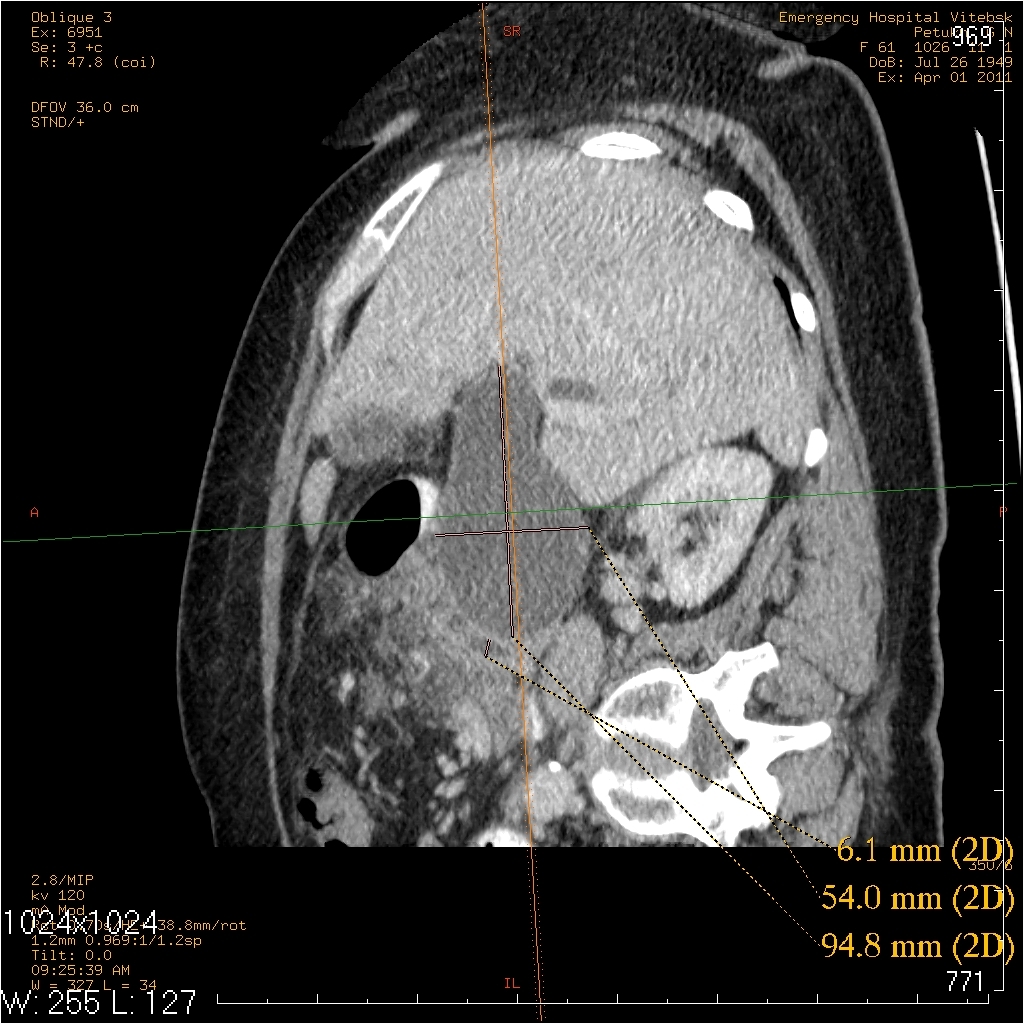

жалобы на периодические боли в правом подреберье, желтушность кожных покровов. считает себя больной в течении 2лет, когда впервые появились боли в правом подреберье. госпитализирована 25.03., 31.03. произведено МСКТ, реконструктивная операция 31.03.

На МСКТ: Киста холедоха (грушевидной формы ~95х50мм). ЖКБ: холецистит, холедохолитиаз (в области БДС дефект наполнения просвета 12пк, расширение вирсунгова протока до 10мм). Билиарная гипертензия. Отёчный панкреатит, парапанкреатит.

На операции: Киста холедоха (терминальный отдел холедоха 2мм). ЖКБ: хр.холецистит, холедохолитиаз (конкременты до 4мм). Стеноз папилы 3ст. (блокада вирсунгова протока, общий желчный и панкреатический протоки впадают в двенадцатиперстную кишку по отдельности). Острый панкреатит, парапанкреатит.